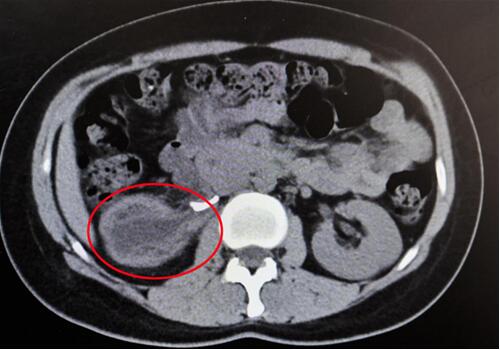

紅圈部分為手術(shù)前腎積水情況。院方供圖

“腎臟就像是一個(gè)皮球,因輸尿管完全閉鎖,里面的積水無法排出、越積越多,已經(jīng)把表皮撐得很薄,在造影下甚至都看不清邊緣了。”靳文生主任說,“由于之前手術(shù)的粘連嚴(yán)重,手術(shù)難度頗大,腎臟能否保住是個(gè)未知數(shù)。”